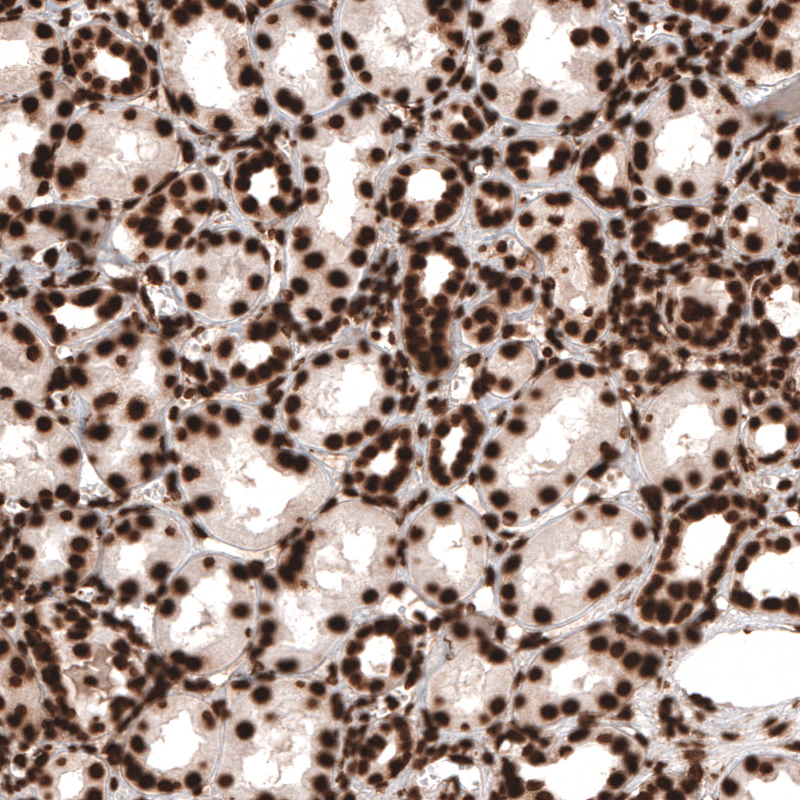

Immunohistochemical staining of human testis shows strong nuclear positivity in cells in seminiferous tubules.